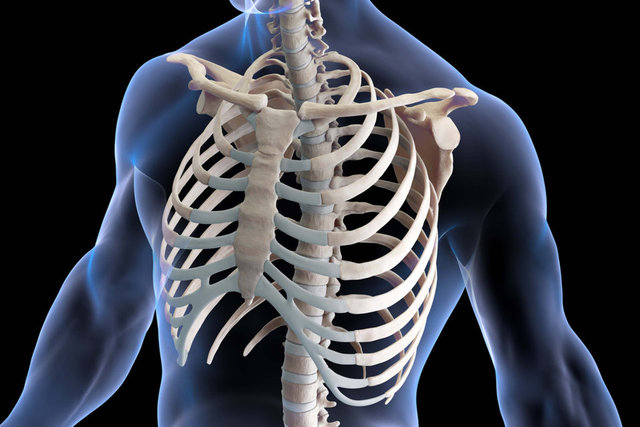

KABURGA KEMİĞİ

Çoğu insanda 12 çift kaburga kemiği vardır yani toplamda 24 kaburga bulunur. Ancak bazı insanlarda bu sayı 25 olabilir. Köprücük kemiğinin üzerinde bulunabilir.